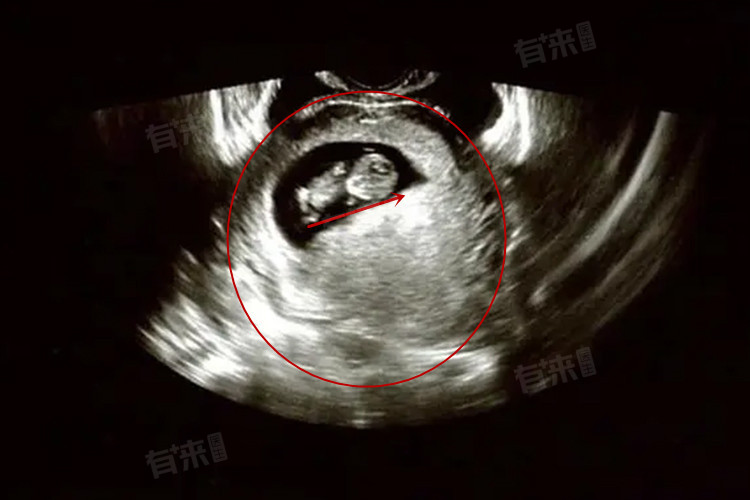

2、手术流产:当药物流产不适合或无效时,手术流产是一种可靠的替代方案,吸宫术是最常用的手术流产方式之一,适用于怀孕10周以内的孕妇。手术过程中,医生会在局部麻醉下使用吸管清除子宫内的胚胎组织。手术流产的成功率高,但仍需遵循医生的术后护理指导,以减少感染风险。